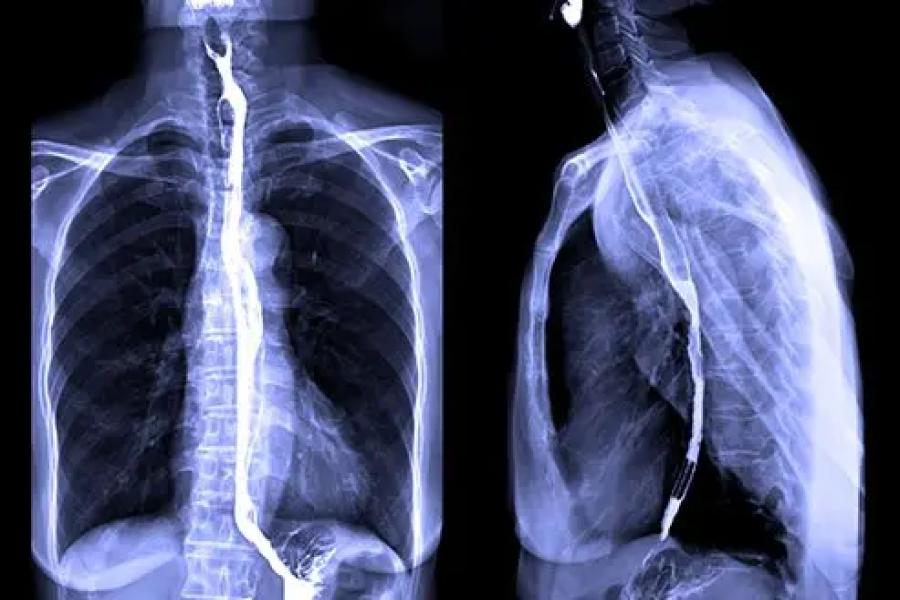

Barium Swallow

Helps identify structural issues like a hiatal hernia.